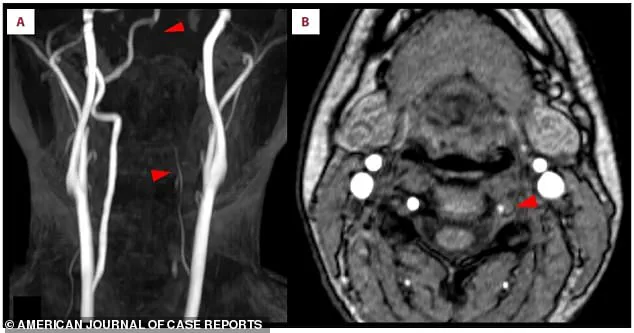

Doctors, upon examining her brain scans, discovered acute ischemic stroke in the right occipital lobe, a region critical for visual processing.

The MRI images, marked with arrows, revealed bright white spots—evidence of brain tissue deprived of oxygen due to blocked blood flow.

The scans also exposed a more ominous detail: a missing section of the right posterior cerebral artery, the key blood vessel supplying the brain.

This artery, normally a smooth, continuous line, had a distinct gap, indicating a blockage.

Further investigation revealed a crescent-shaped blood clot embedded within the left vertebral artery, a vital conduit for blood to reach the brain.

This artery, visible in the scans, appeared faint and thin, signaling restricted blood flow.